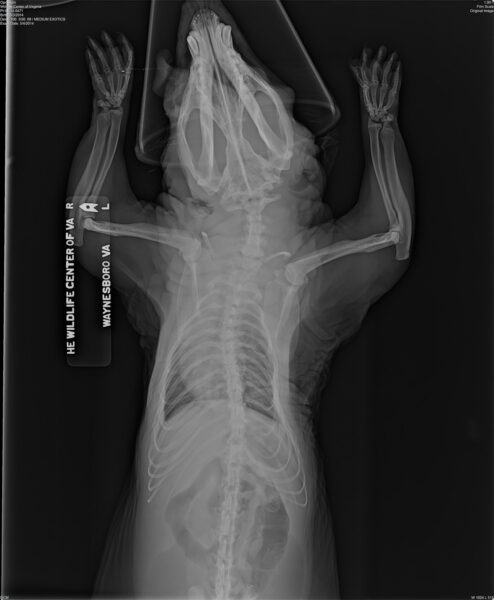

Ang x-ray na ito ng isang opossum na pinananatiling bihag ay nagpapakita ng mga abnormalidad ng buto—kurbada sa mga binti at gulugod—na kadalasang nangyayari kapag ang mga bihag na hayop ay pinapakain ng hindi naaangkop na diyeta ng mga hindi sinanay na indibidwal. Sa kagandahang-loob ng The Wildlife Center of Virginia